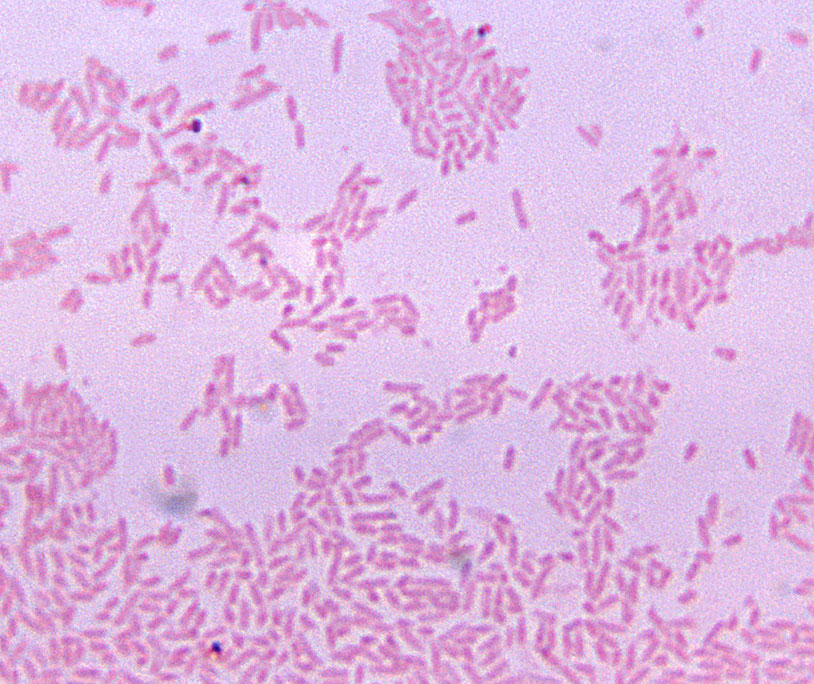

gram negative bacilli

Your Gram stain is complete and correct. Which of the following statements would apply to the image you see?

unknown is negative, as S.aureus is known positive, so it can be ruled out

One initial suspect bacteria you considered was the common sepsis (bloodstream infection) organism Staphylococcus aureus. Why can we rule this organism out as the cause in the patient?

gram positive cocci

Your Gram stain is complete and correct. Which of the following would apply to the image you see?

gram stain is positive, suggests streptococci. H influenzae is gram neg/ruled out

One initial suspect bacteria you considered was the common otitis media bacterium Haemophilus influenzae. Why can we rule this organism out as the cause in the patient?